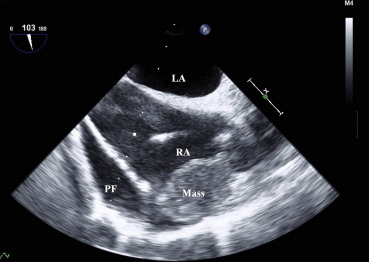

TEE revealed massive pericardial effusion over the right heart and a redundant motion of the right atrial free wall, and showed a 3.5 × 2.5 cm mass with bright echodensity in the lateral wall of the right atrium adjacent to the superior vena cava (Fig. 2). Moreover, after sternotomy, the ascending aorta showed no surgical pathology. Then, the surgical plan was changed for a resection of the right atrial mass. For the right atrial mass excision, another 24F venous cannula was inserted at the superior vena cava and antegrade cold blood cardioplegia was infused via a root cannula for myocardial protection.

Transesophageal echocardiography reveals massive pericardial fluid collection ...

Figure 2.

Transesophageal echocardiography reveals massive pericardial fluid collection over the right heart and redundant motion of the right atrial free wall and shows a 3.5 × 2.5 cm mass in the lateral wall of the right atrium. LA = left atrium; PF = pericardial fluid; RA = right atrium.